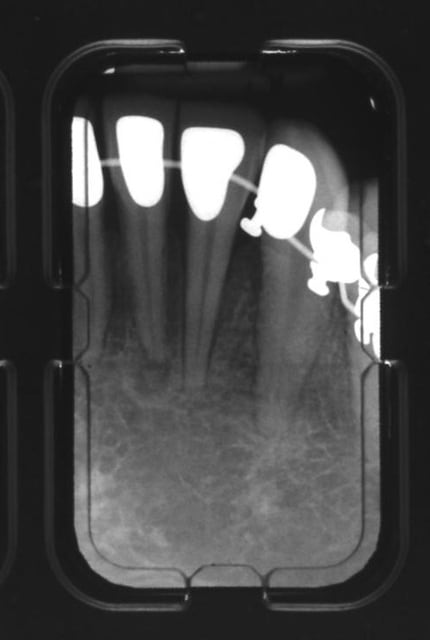

mes radios, à J + 3 mois...

(ben quoi? je vérifie le boulot de l'autre ;-))

Mr le radiologue (Gérard Pasquet de son nom, vous savez le Mr du bouquin de radiologie :-)) s'inquiète pour ma 31/ trouve que j'ai une image apicale au bout...moi pas trop...

Vous en pensez quoi?

et puis regardez ma 21, comme elle aime pas tout ce qu'elle subit :-((((

tu peux poster uniquement les rétros de 21 et 31, trop petit comme ceci